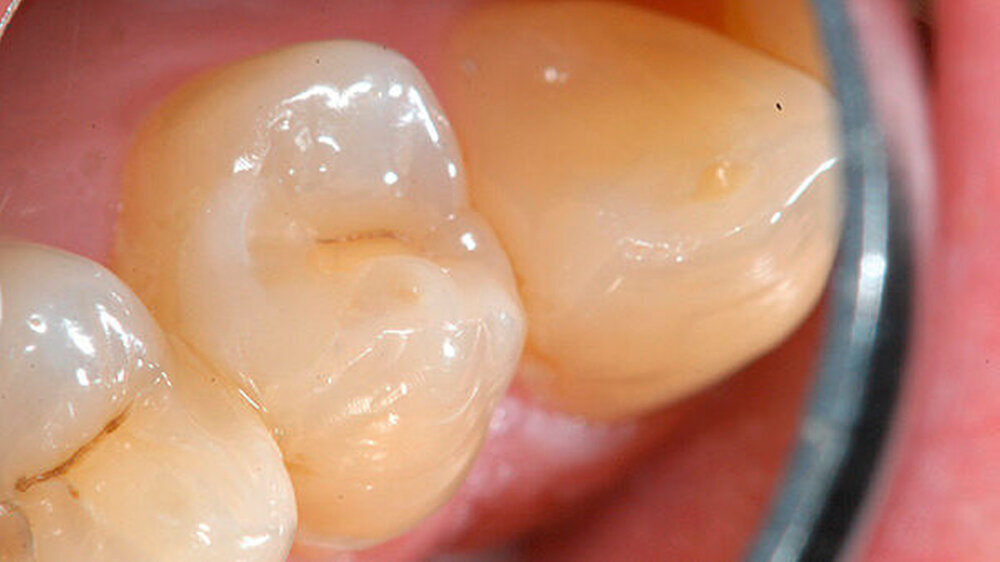

Nach dem initialen Abbinden des Materials wurden auf die gesamte Kavität einschließlich der Zementoberfläche ein selbstätzendes Dentinadhäsiv (Optibond XTR; Kerr, Bioggio, Schweiz) aufgetragen und eine Kompositfüllung (Grandio; VOCO, Cuxhaven) gelegt (Abbildung 9 und 10).

Bei den Kontrolluntersuchungen sechs und 26 Monate nach direkter Überkappung war der Zahn 14 klinisch unauffällig (Abbildung 11) und zeigte sich wiederum bei der Sensibilitätsprobe mit CO

2

-Schnee positiv und bei der Perkussionsprobe negativ.

Auf dem 26 Monate nach direkter Überkappung angefertigten Zahnfilm konnten apikal an Zahn 14 keine pathologischen Veränderungen festgestellt werden (Abbildung 12). Dem Patienten zufolge war es zu keinem Zeitpunkt, zum Beispiel im Kontakt mit kalter Nahrung, Flüssigkeit oder Luft, nach der direkten Überkappung zu Beschwerden an Zahn 14 gekommen.